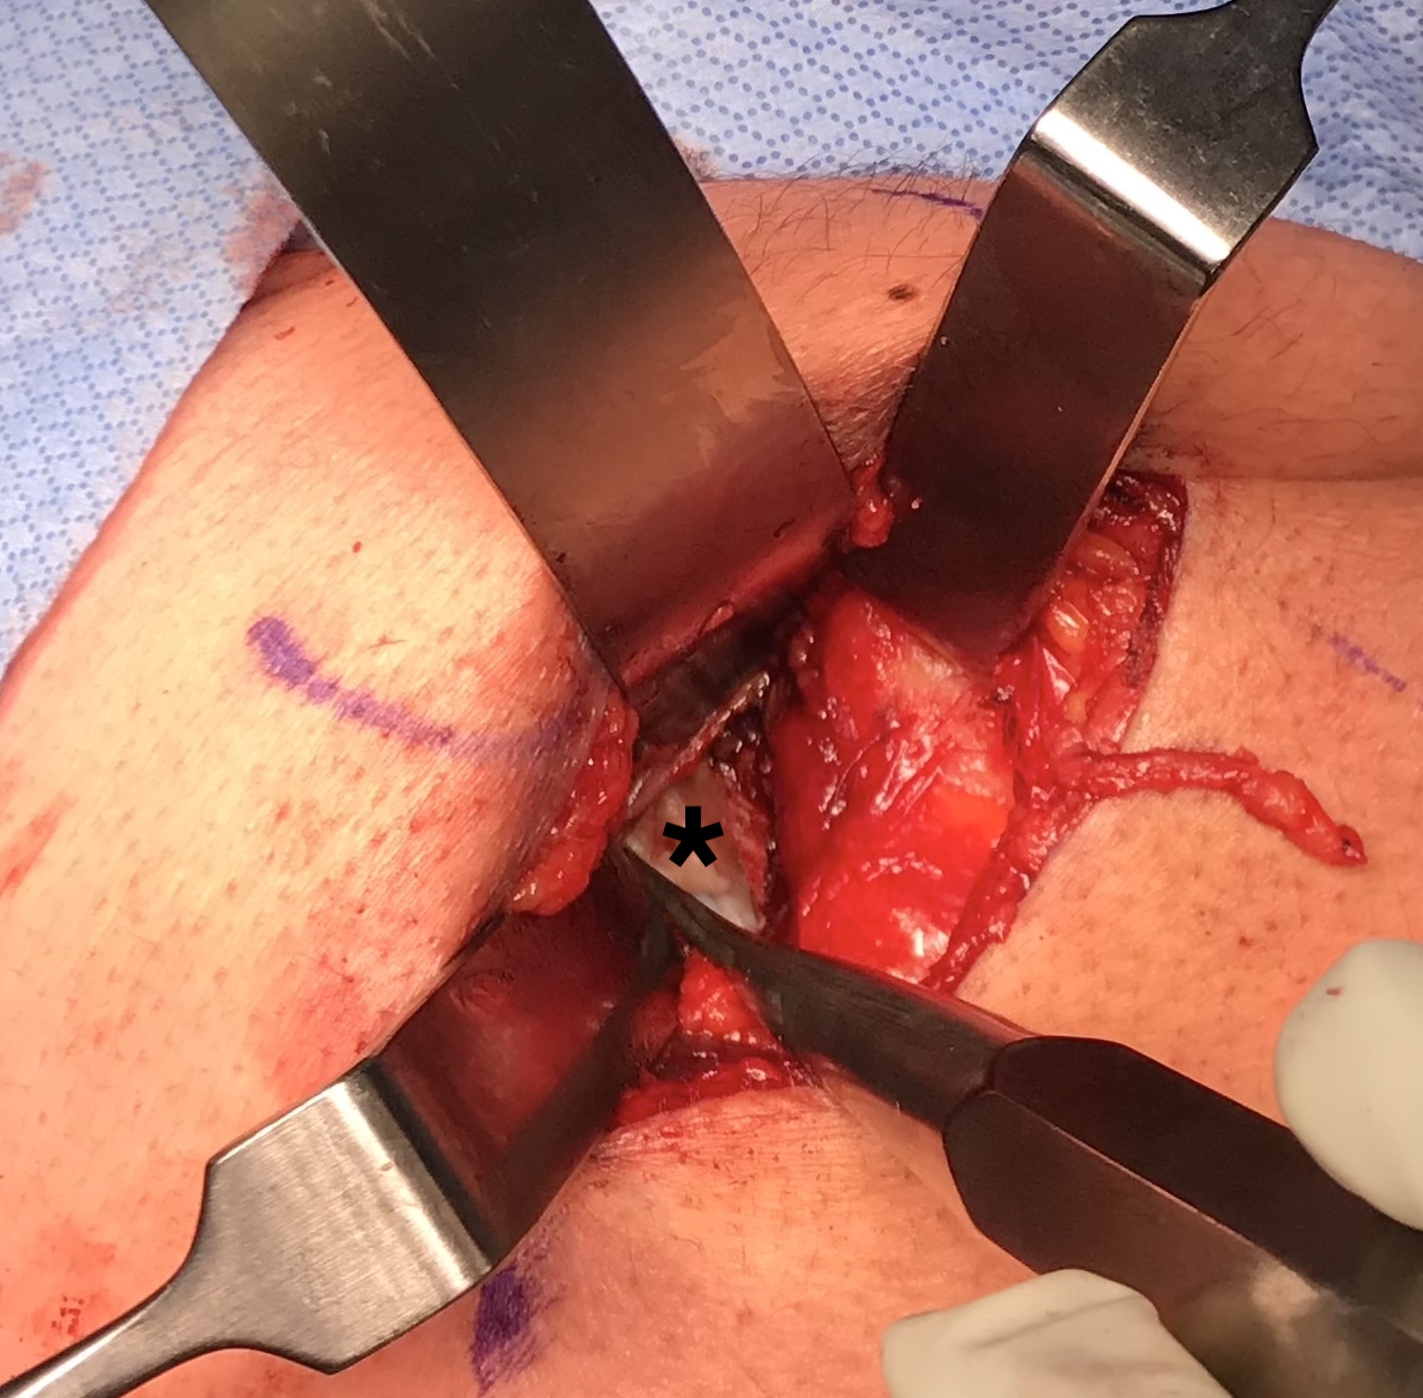

Elevate high grade tear with Cobb, exposing bare ischial tuberosity (*)